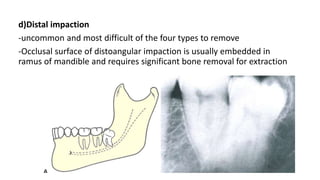

d)Distal impaction

-uncommon and most difficult of the four types to remove

-Occlusal surface of distoangular impaction is usually embedded in

ramus of mandible and requires significant bone removal for extraction